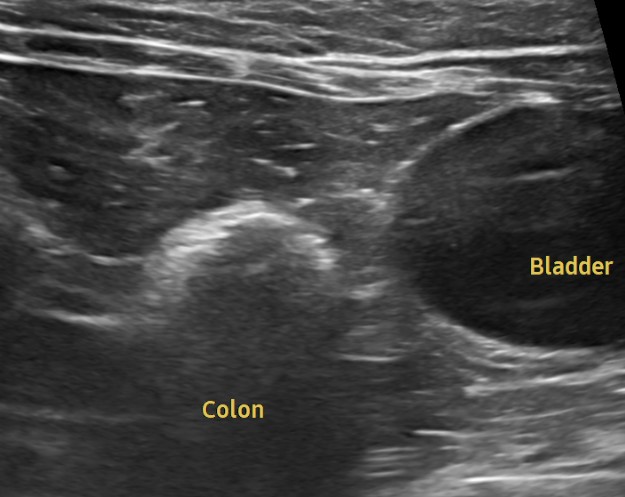

혈액검사에서는 주요 장기 수치, 염증 수치, 전해질 균형 등을 확인했고, X-ray는 흉부·복부 전반의 장기 구조를 점검했습니다. 초음파는 장기 실질 구조나 미세한 이상까지 확인할 수 있어 검진의 핵심 항목으로 포함됩니다. 치과검사는 일반적으로 마취가 동반되어, 구강전용 엑스레이 촬영을 해야 정확한 판단이 가능하지만 치과전문 병원인 만큼 육안으로 기본적인 검사는 해드리고 있습니다.